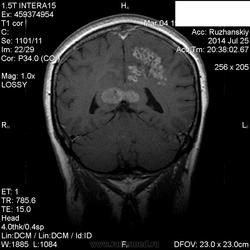

Мама приятельницы.Нарушение походки в течение 2-3 месяцев.

DDs: рассеянный склероз, токсоплазмоз, mts.

Рассеянный склероз вряд ли. Я бы добавила лимфому и глиобластому.

Думается больше о глиобластоме в форме бабочки. Из книги "Диагностическая нейрорадиология". Корниенко, Пронин.

На РС точно не похоже. Токсоплазмоз - навряд ли, т.к. "мама приятельницы", а это чаще всего бывает у ВИЧ-инфицированных.

+1 к глиобластоме.

Сегодня узнала: нейрохирурги за лимфому.Сделали КТ и подтвердили .

Сейчас  уточняют план лечения.